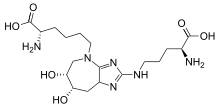

Proteins are usually glycated through their lysine residues.[29] In humans, histones in the cell nucleus are richest in lysine, and therefore form the glycated protein N(6)-Carboxymethyllysine (CML).[29]

Compounds that have been found to inhibit AGE formation in the laboratory include Vitamin C, Agmatine, benfotiamine, pyridoxamine, alpha-lipoic acid,[38][39] taurine,[40] pimagedine,[41] aspirin,[42][43] carnosine,[44] metformin,[45] pioglitazone,[45] and pentoxifylline.[45] Activation of the TRPA-1 receptor by lipoic acid or podocarpic acid has been shown to reduce the levels of AGES by enhancing the detoxification of methylglyoxal, a major precursor of several AGEs.[38]